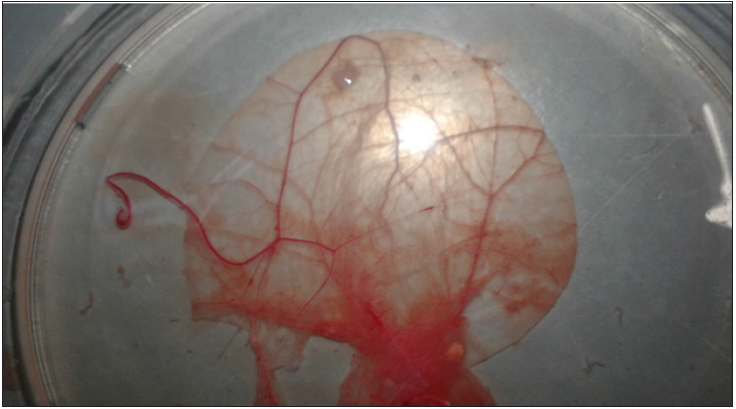

Viral isolation and identification in fertile eggsILTV was isolated on chorioallantoic membrane (CAM). Inoculation of chicken fertile eggs on CAM with samples from cases 1 and 3 revealed presence of congestion, hemorrhages and pock lesions after 5 days post inoculation (Figure 1). Samples from other cases were negative (Figure 2).

Figure 1: CAM showing congestion, hemorrhages and pock lesions after 5 days post inoculation.